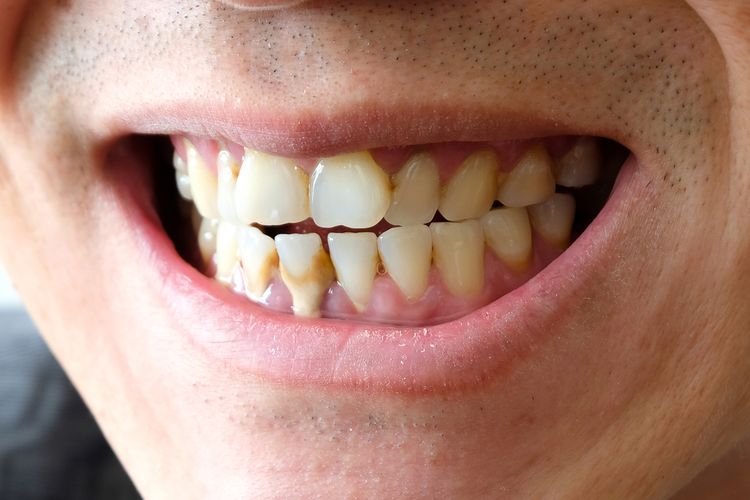

Akan tetapi bukan berarti penyakit gigi ini. Gigi berlubang adalah kondisi gigi yang rusak akibat terkikisnya lapisan terluar gigi enamel. Kenapa Gigi Berlubang Menyakitkan.

. Gigi berlubang merupakan keluhan pada gigi yang umum terjadi baik pada orang dewasa maupun anak-anak. Kondisi ini disebabkan oleh penumpukan bakteri di mulut akibat sering mengonsumsi makanan manis dan tidak menjaga kebersihan mulut. Asam dalam lemon berfungsi sebagai alkali alami agar kadar pH dalam mulut jadi seimbang.

Makanan dan minuman ini cenderung bertahan dan menyebabkan. Rutin menyikat gigi Anda selama 2 menit pada pagi dan malam hari sebelum tidur adalah cara terbaik untuk mencegah gigi berlubang. Gigi berlubang biasanya sering diderita oleh anak kecil namun orang dewasa juga bisa menderita masalah gigi berlubang.